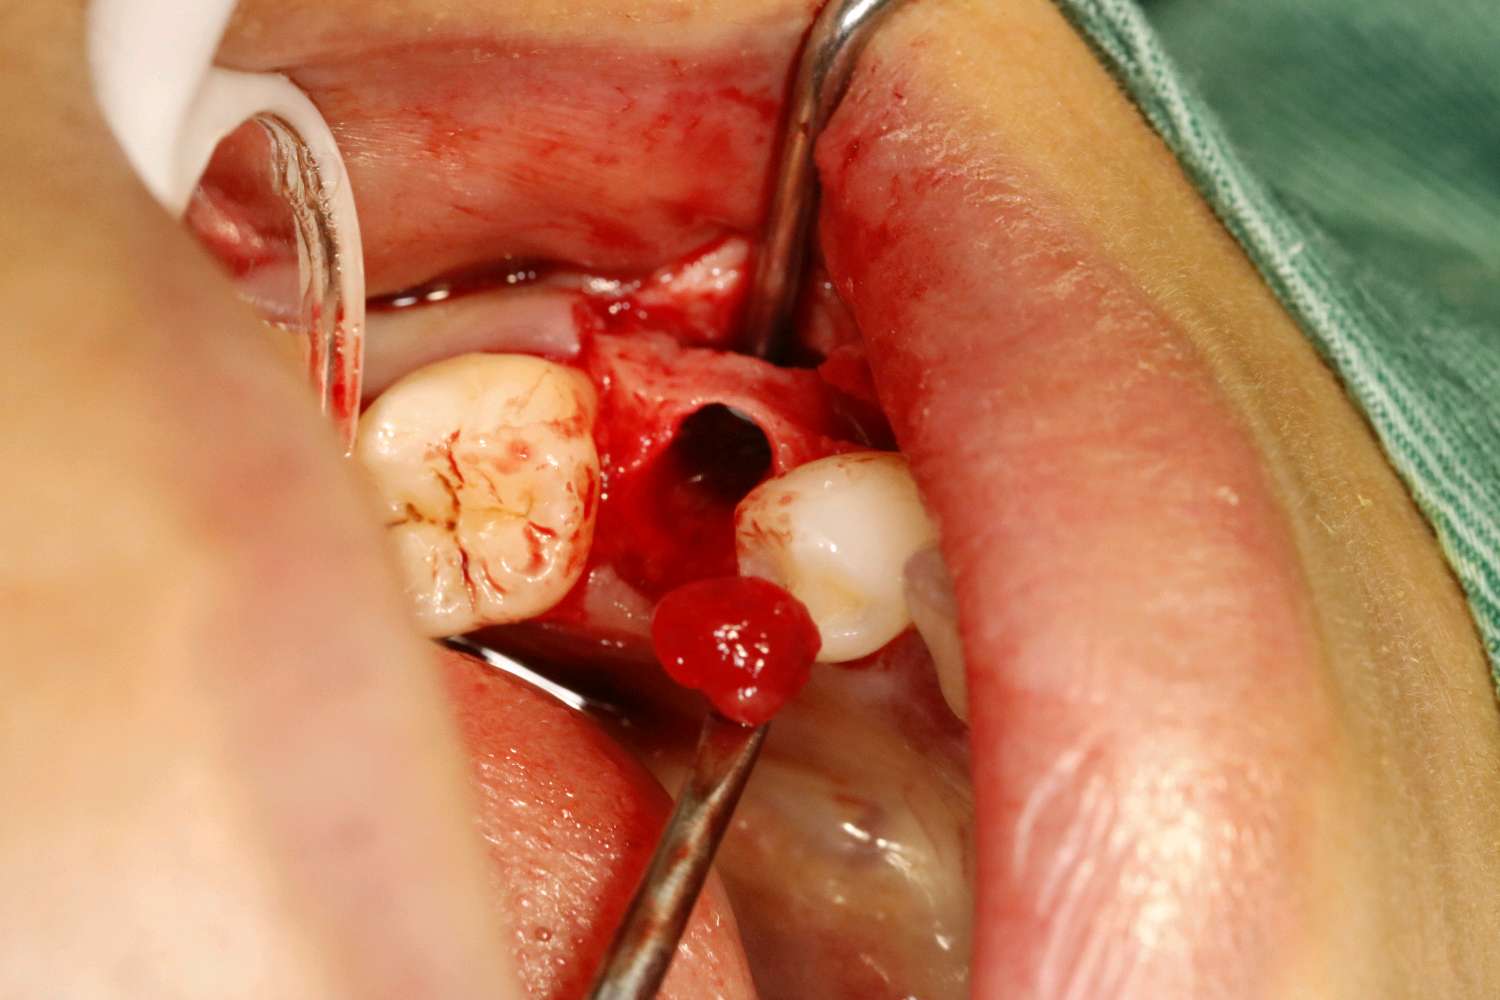

患者女三十岁,35畸形中央尖折断,根尖周炎症感染,导致牙根发育停止,根尖口呈喇叭口状。拔出后搔刮牙槽窝,颊侧骨壁吸收,植入骨粉骨膜。定期复查,将近半年见骨密度良好,骨量充足的条件下,行种植手术。植入3I 4/3*11.5mm的种植体。二期三期如期进行,与今日戴牙,患者满意。

术后